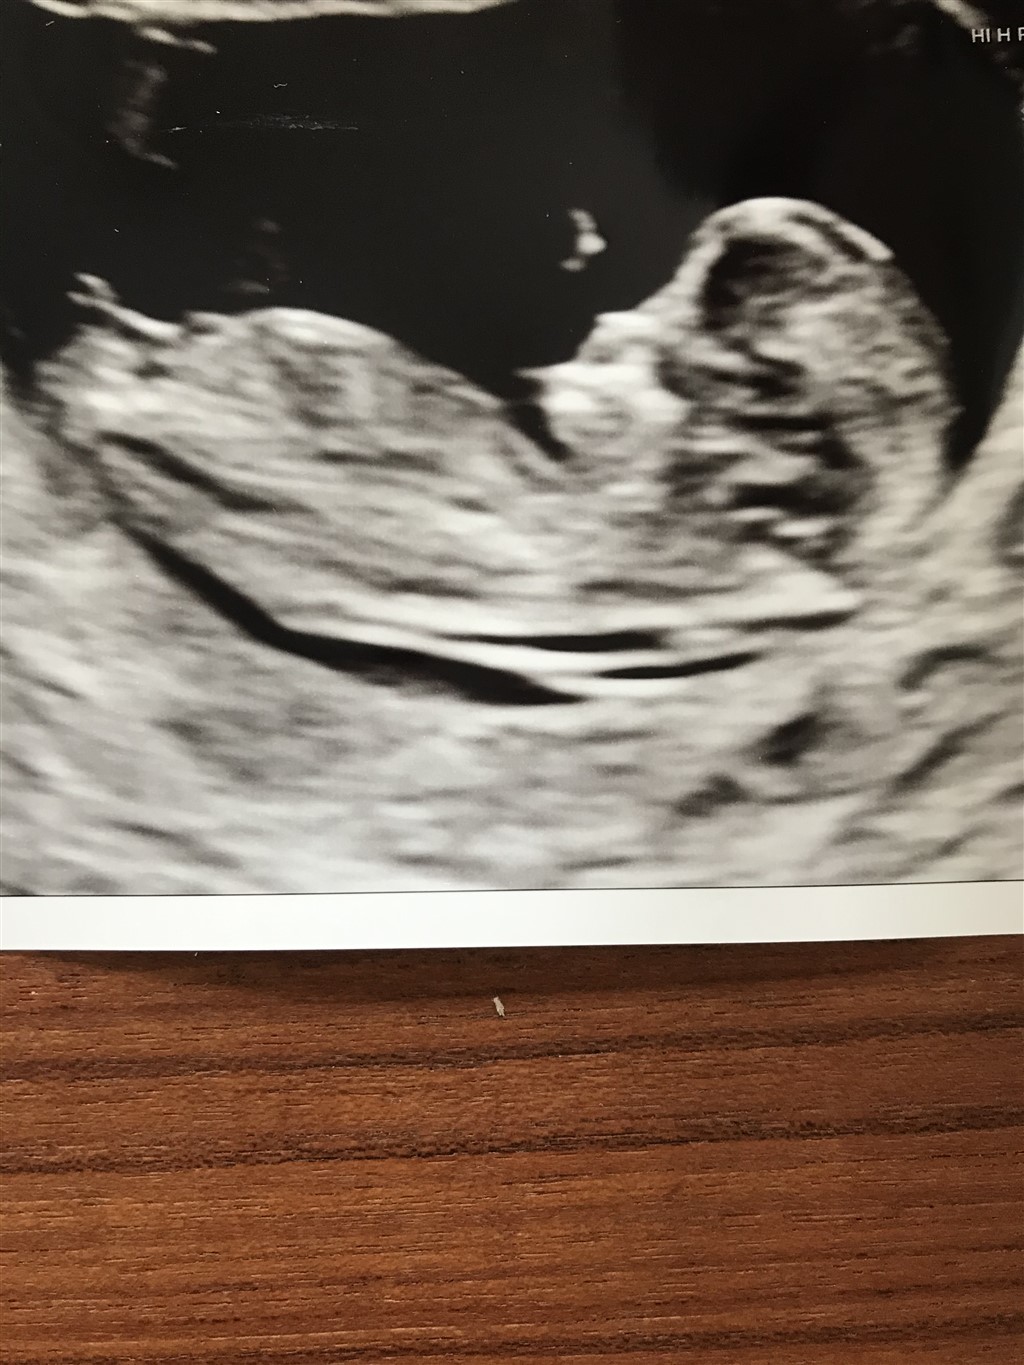

Kan I se noget som helst på dette billede? Den lille er kun 11+3

Pige

Kan man ikke først se det efter 12+0? Før det ligner alle vist piger.